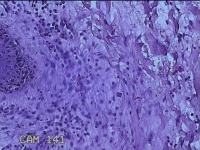

左侧会阴部结节

性别

女

年龄

43岁

临床诊断

皮肤良性肿瘤

一般病史

发现右侧会阴部结节3年余。

标本名称

大体所见

灰白粉红色带皮肤结节0.8x0.7x0.3cm一个,表面光滑,切开结节呈实性,切面灰白粉红色,质韧。